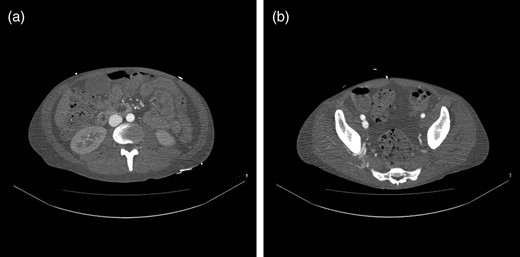

Two weeks postoperatively, reinvestigation of previous CT scans showed rapid contrast filling in the inferior caval vein (Fig. 1a) as well as the right common iliac vein (Fig. 1b), almost simultaneously with the abdominal aorta. Recent CT scans showed dissolution of most of the right-sided, ileofemoral deep vein thrombus. Right groin palpation revealed fremissement. Doppler ultrasound demonstrated an unusually large arteriovenous (AV) fistula localized between the cranial part of the superficial femoral artery and the femoral vein. Flow in the fistula was estimated as 11.2 l/min.

(a) CT scan demonstrating rapid contrast filling of the vena cava. (b) CT scan demonstrating contrast filling of the right common iliac vein.